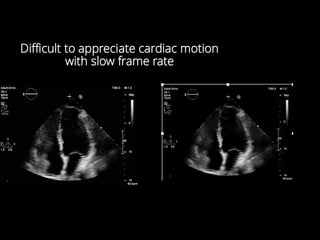

Temporal Resolution Ability toaccurately display events in real-time Rule - All the ultrasound from any given pulse must return to the transducer before the next pulse. Temporal resolution can be appreciated by observing the Frame Rate CARDIAC IMAGING IS ALL ABOUT THE FRAME RATE

Difficult to appreciatecardiac motion with slow frame rate

Higher frame rateLower frame rate shallow deep single focus multi focus ( lat res) narrow sector wide sector low line density hi line d’sity ( spat’l res) SUMMARY - TEMPORAL RESOLUTION